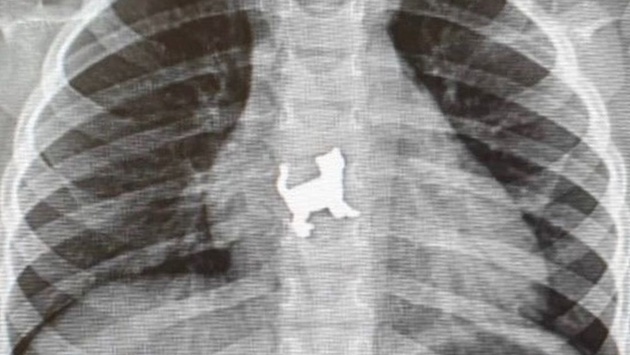

Ее привезли в Республиканскую детскую клиническую больницу с жалобами на боли в грудной области. Родители сказали, что во время игры малышка случайно проглотила металлическую игрушку в форме кошки. В экстренном порядке хирурги провели ригидную эзофагоскопию и удалили инородное тело.